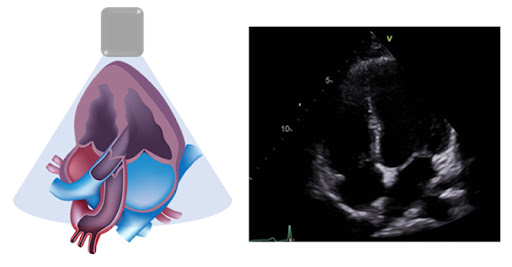

- 심장 질환: 심장이 혈액을 효과적으로 펌프하지 못할 경우 가슴이 답답하거나 숨이 차는 증상을 겪을 수 있습니다. 예를 들어, 심부전이나 심근경색은 이러한 증상을 일으킬 수 있는 대표적인 질환입니다.